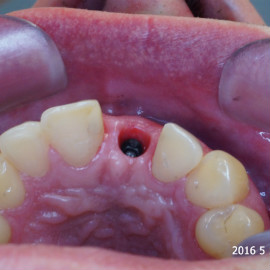

Pacjent z długą historią leczenia implantologicznego. Pierwsze implanty w pozycjach 23, 24 miał wkręcane w Warszawie przed 25 laty. Implant w pozycji górnego prawego kła ma agresywny gwint, ponieważ bezpośrednio po implantacji był obciążony (immediate loading) tymczasowym atachmentem ball abutmentv do stabilizacji tymczasowej protezy ruchomej. Kość szczęki regenerowana i odbudowywana etapami w całym górnym prawym kwadrancie. Pacjent planuje uzupełnić brakujące zęby 25, 26.